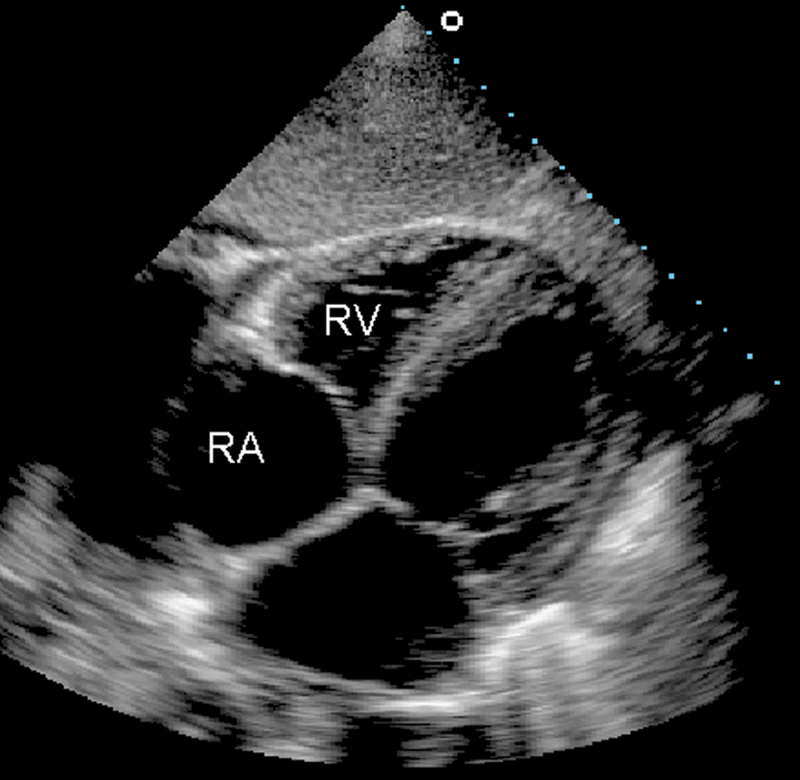

فحوصات تشخيصية لبعض امراض القلب والشرايين التاجية